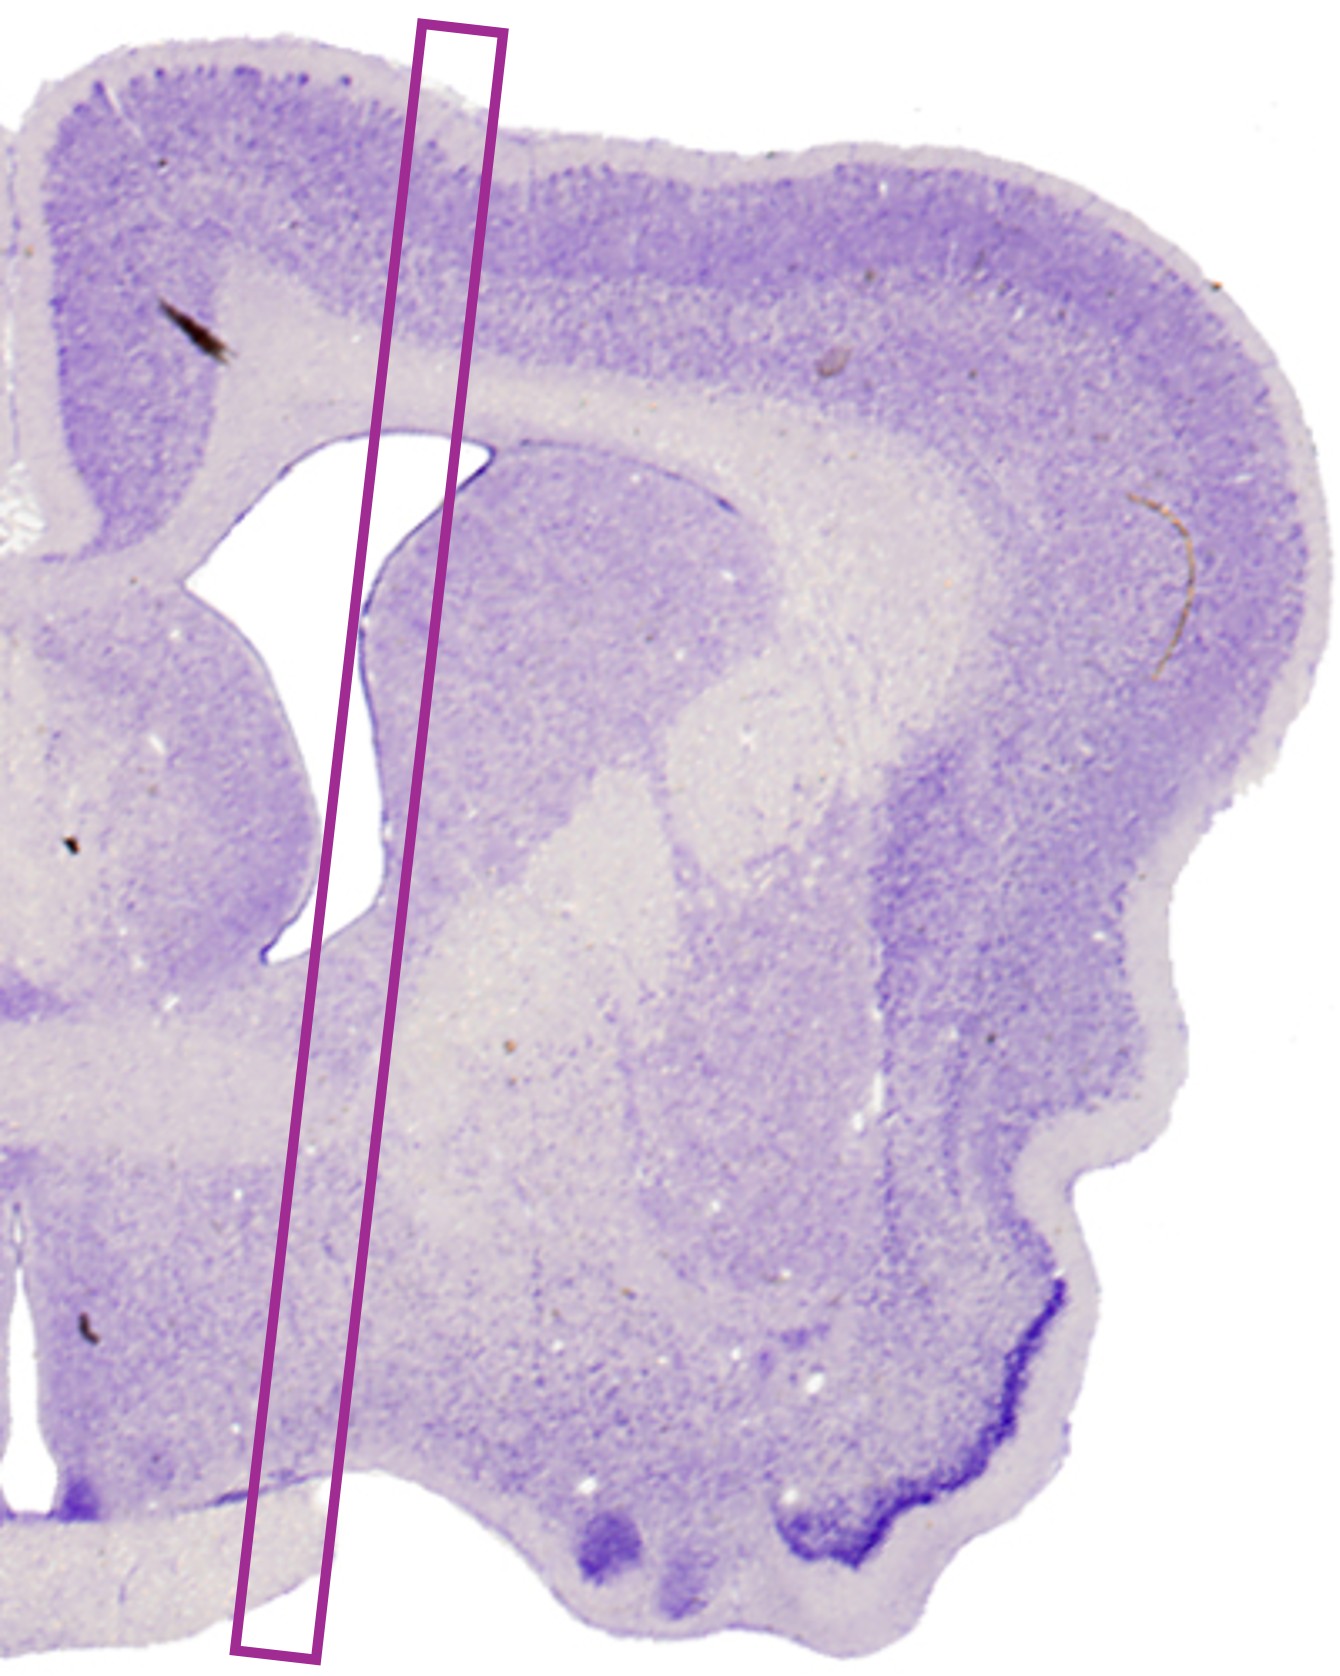

Histology

H&E

Brain surgery traditionally relies on pre-operative MRI imaging, which often falls short in enabling precise targeting during procedures. At Clee Medical, we’ve developed a groundbreaking solution: real-time, ultra-high-resolution brain visualization during surgery—live, without the need for contrast agents or radiation. We are setting a new standard in neuroimaging, seamlessly bridging the gap between preoperative diagnostics and real-time surgical precision.

15 micrometers - 300,000 more voxels per unit volume than MRI.